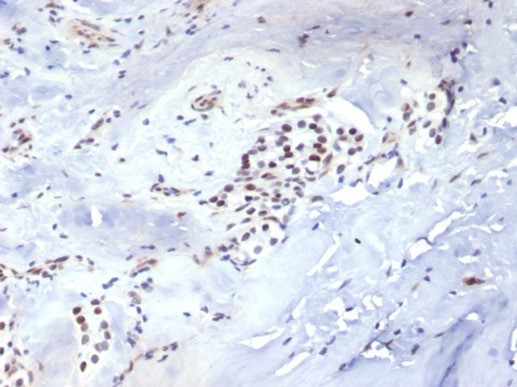

TBXT/T-box transcription factor T/Brachyury Antibody in Immunohistochemistry (Paraffin) (IHC (P))

TBXT/T-box transcription factor T/Brachyury Antibody (6862-RBM2-P0) in IHC (P)

Formalin-fixed, paraffin-embedded human parathyroid stained with TBXT Recombinant Rabbit Monoclonal Antibody (TBXT/7711R). HIER: Tris/EDTA, pH9.0, 45 min. 2 °: HRP-polymer, 30 min. DAB, 5 min. {{ $ctrl.currentElement.advancedVerification.fullName }} 验证信息 View more